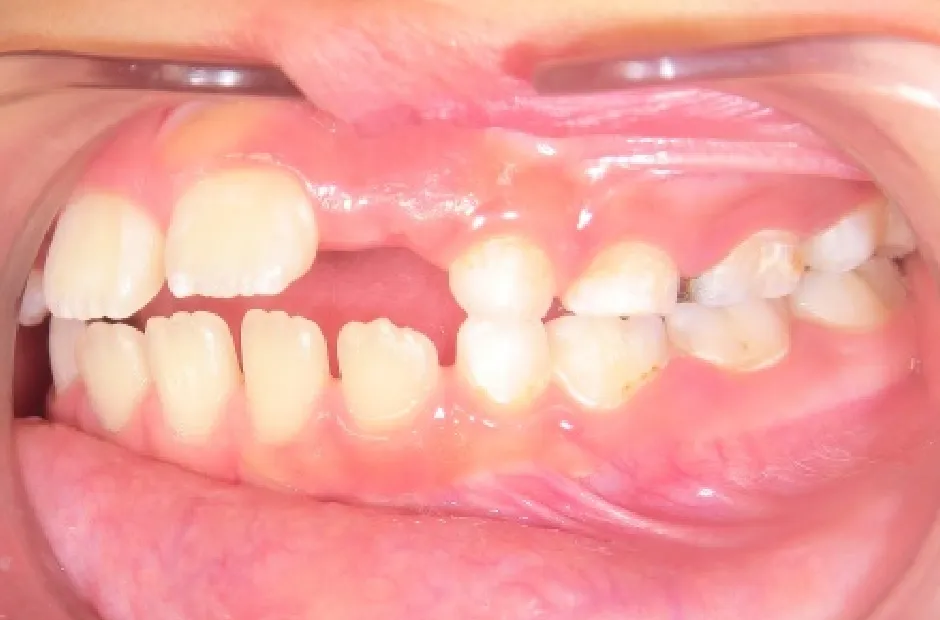

叢生

| 診断名・主訴 | 叢生 |

|---|---|

| 年齢・性別 | 10歳・女性 |

| 治療期間・回数 | 2年半 |

| 治療に用いた主な装置 | 拡大床装置 |

| 抜歯部位 | なし |

| 治療費 | 30万円(税抜) |

| リスク・副作用 | 装置による違和感・疼痛・歯肉退縮・歯根吸収・虫歯のリスクなど |

治療前

治療中

治療後